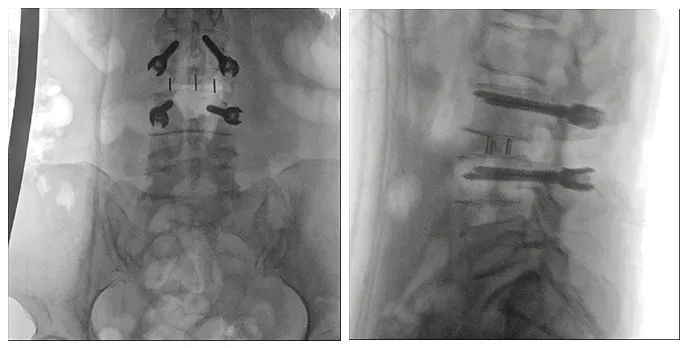

患者一個月前因雙側下肢疼痛至醫院就診,診斷為腰椎間盤突出。患者自行至診所就診,予以推拿牽引術,疼痛未明顯緩解,到醫院進一步治療。影像診斷:L3-4椎間盤突出,椎管變窄(中央型)。

術前影像

使用普愛醫療術中三維導航C臂進行透視,根據透視影像引導確認責任間盤、規劃手術方案,充分暴露骨組織,并通過專業器械切除椎板,暴露神經及椎管;在C形臂的引導下,確定責任間盤上下椎體椎弓根位置,制定進針點及進針方向,沿椎弓根方向植入脊柱螺釘進行固定;放入椎間融合器,加固螺釘。最后再進行C形臂透視,確認手術的完成效果。

手術效果確認